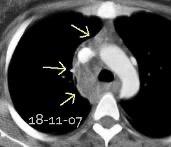

Linfoma de Hodgkin escleroso-nodular

Mediastinitis fibrosa. Fibrosis retroperitoneal.

10-20% de los casos de FM difusa

Reacción a Enf. Autoinmunes. (LED, AR)

Hematopoyesis extramedular

Metersigida / Radioterapia. Enf. inmunoglobulina IgG4. (Riedel, Colangitis, etc.)